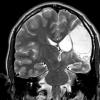

4A4 Porencephaly (Case 4) T2 3 - Copy